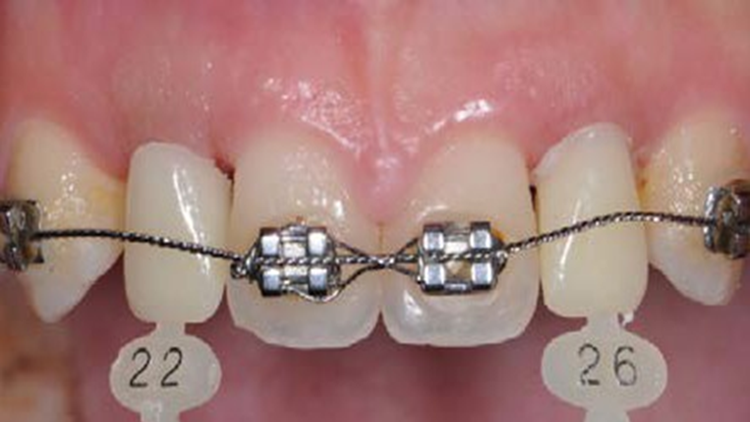

Clinical case: 3.0 mm MiNi implants placement at #12, #22

- Courtesy of Dr. Achraf Souayah, Tunise -

Keywords

Anterior esthetics, MiNi, flap elevation, minimally invasive technique, soft tissue management, esthetic zone, Dr. Achraf Souayah, anterior aesthetics, aesthetic, aesthetics, esthetic, #12, #22

Products:

MiNi implant system